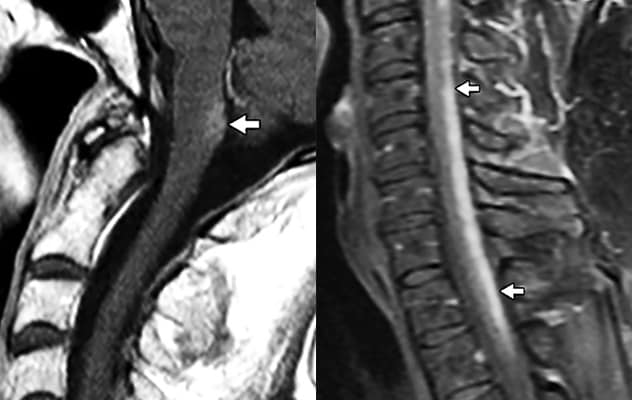

在左图中,MRI 显示 AQP4 富集的极后区存在病变,这是某些 NMOSD 患者的特征。在右图中,一名结节病患者的 MRI 显示了两种医疗状况的不同影像学特征。

Diagnostic criteria for NMOSD require the manifestation of at least one of six core clinical syndromes. MRI is used to detect lesions characteristic of NMOSD in the brain, optic nerve, optic chiasm or spinal cord. A serum assay can establish the presence of AQP4-IgG autoantibodies.